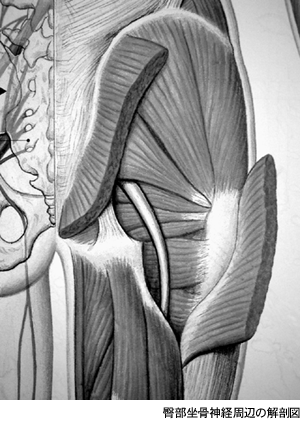

ご質問の障害はいわゆる梨状筋症候群だと思われます。股関節の動きのなかでも特に繊細であり、かつ微力なものに内、外旋運動があります。股関節を内旋すると痛むということは、外旋筋群が短縮して硬くなっているため、その下にある坐骨〈ざこつ〉神経が圧迫されている可能性があります。このような疾患を梨状筋症候群(Piriformis syndrome)といいます。

臀部〈でんぶ〉坐骨神経周辺の解剖図

まずは複雑な臀部〈でんぶ〉坐骨神経周辺の解剖図を見てください。